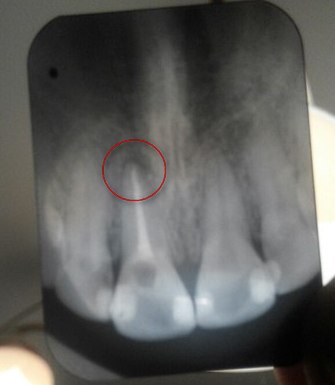

В декабре 2014 запломбировали канал 21 зуба. В тот момент уже была маленькая киста, но доктор сказал, что можно сразу ставить постоянную пломбу, а так как киста очень маленькая, то она рассосется в течение нескольких месяцев. На данный момент ничего не изменилось, снимок актуальный. Зуб ноет только при прикосновении. Пропила курс амоксикара, ходила на лазеротерапию, улучшений нет.

Это не киста, а периодонтит. Данное воспаление имеет хронический характер и без немедленного вмешательства впоследствии зуб можете потерять. По снимку нет следов качественного лечения периодонтита, обратитесь к альтернативному мнению стоматолога-терапевта. Рекомендую записаться к нашему врачу Сусанне Спартаковне, в этом случае вам гарантирован успех.